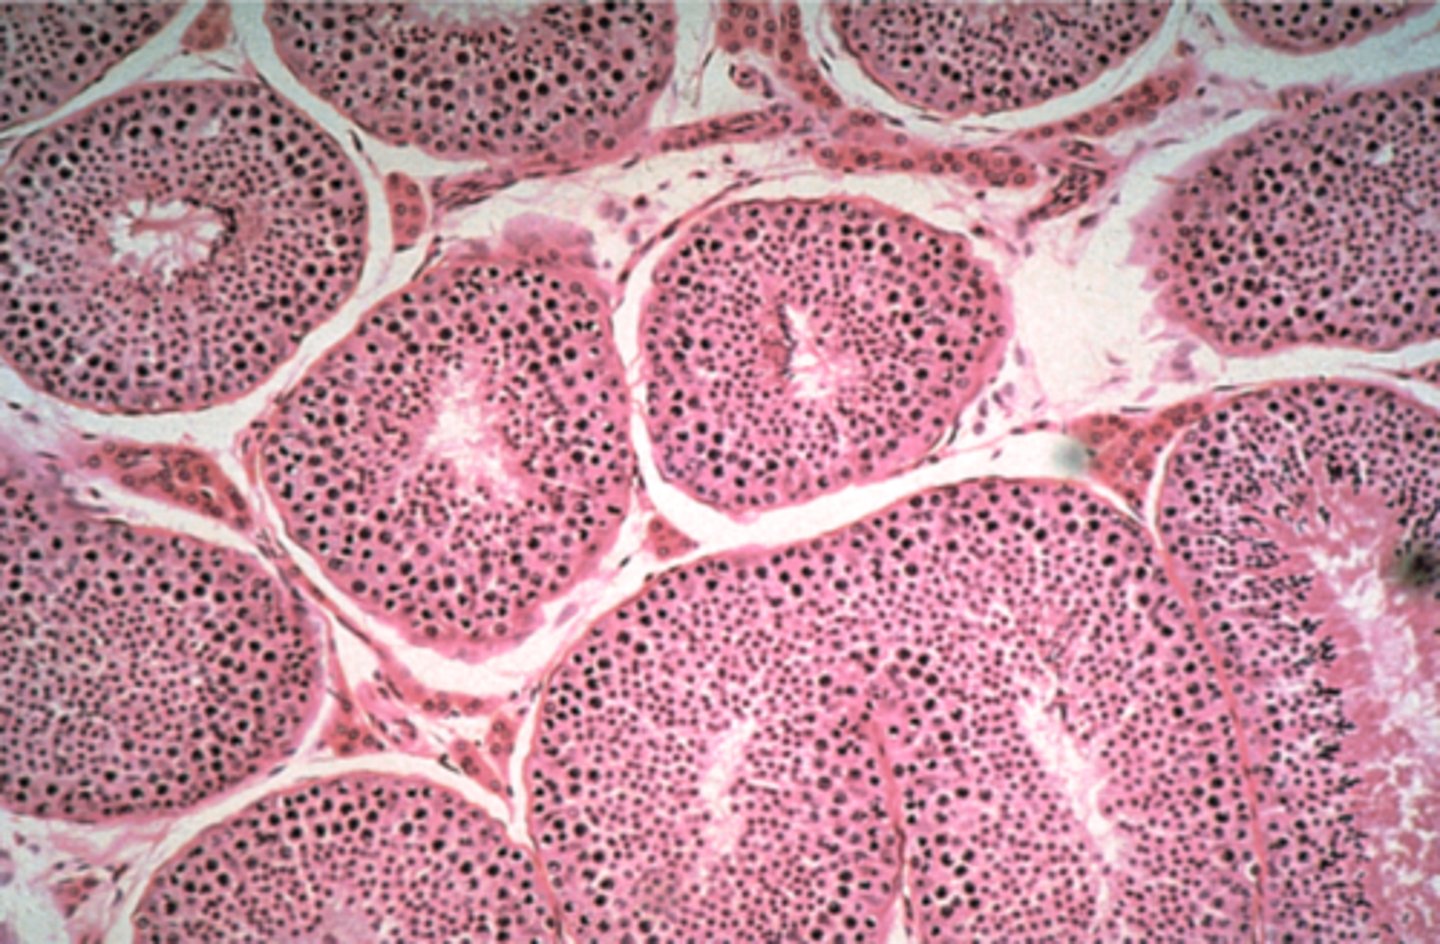

testis

What is this?

testis

What is this?